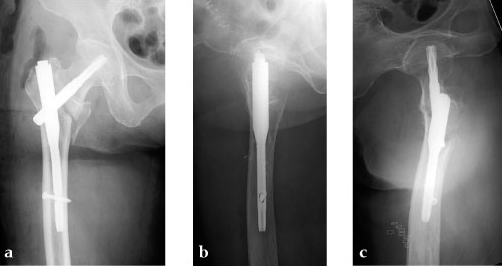

An 85-year-old Japanese woman fell down at her home. She sustained an AO 31-A2.1 fracture. The images indicate various stages of the operation, using the PFNA Asia.